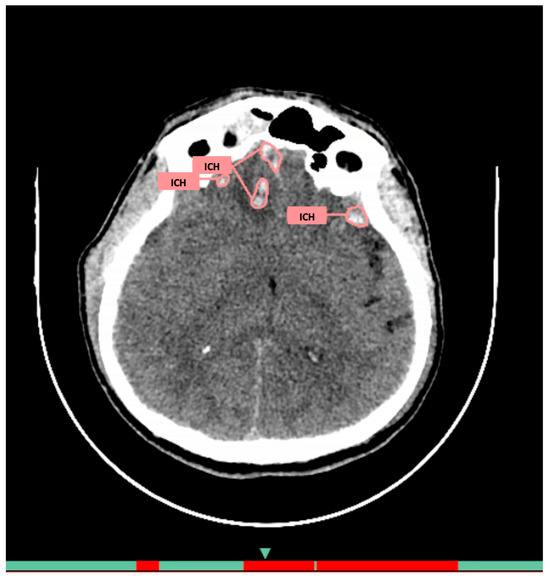

2.4. AI Services

3.1. Comparison of AI Services Among Themselves